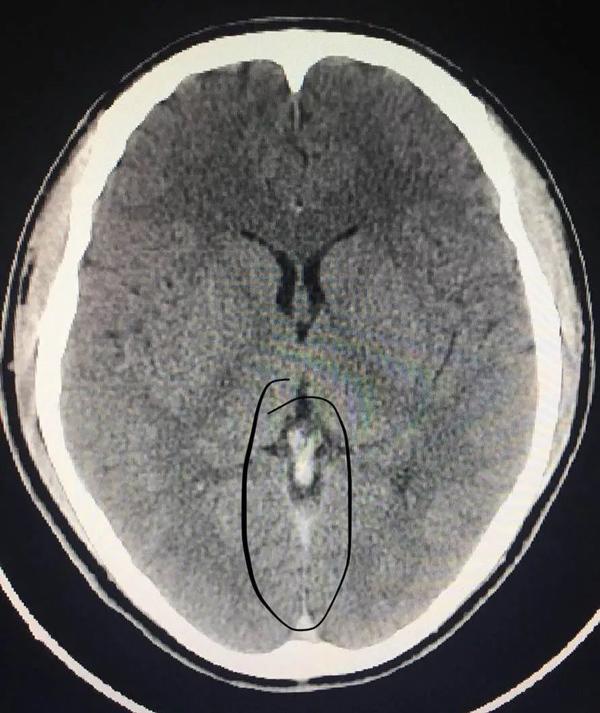

Thông qua kiểm tra CT, bác sĩ Cảnh Anh Triều làm việc tại khoa phẫu thuật thần kinh nhận định Tiêu Hà bị huyết khối tĩnh mạch xoang nội sọ.

Nếu phạm vi tắc nghẽn được mở rộng thêm có thể dẫn tới xuất huyết, đe dọa đến tính mạng. May mắn thay, nhờ đưa tới bệnh viện kịp thời nên các bác sĩ có thể nhanh chóng tiến hành điều trị, các triệu chứng buồn nôn, đau đầu cũng thuyên giảm dần.